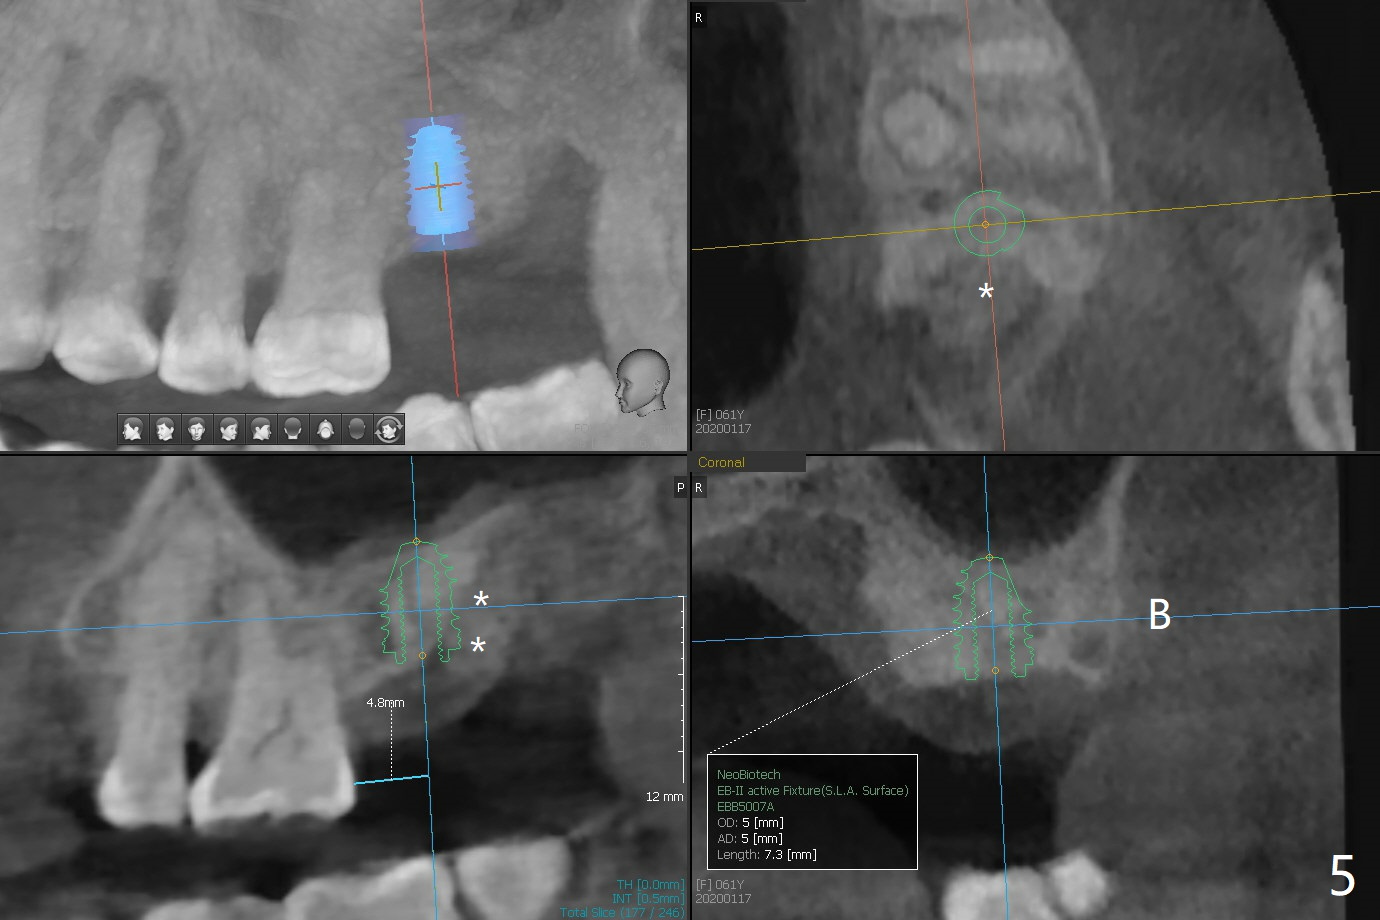

A 61-year-old woman requests #15 implant post ones at #2 and 6 because of pain in mastication (Fig.1). Examination shows that the tooth #16 has advanced periodontitis with mesial bone loss (Fig.1 *). It appears that there is insufficient bone for #15 implant. Bone graft seems necessary at #16 after extraction. There is severe hemorrhage post extraction. Osteogen plug is inserted for hemostasis prior to placement of allograft (Fig.2 *). The socket opening is covered with 12x12 mm Amnion-Chorion Membrane and 5-0 Polysyn. The socket seems to heal 9 days postop (Fig.3). The bone graft in the socket of #16 three months postop (Fig.4 *) will support an implant to be placed at #15 distal (Fig.5 *).